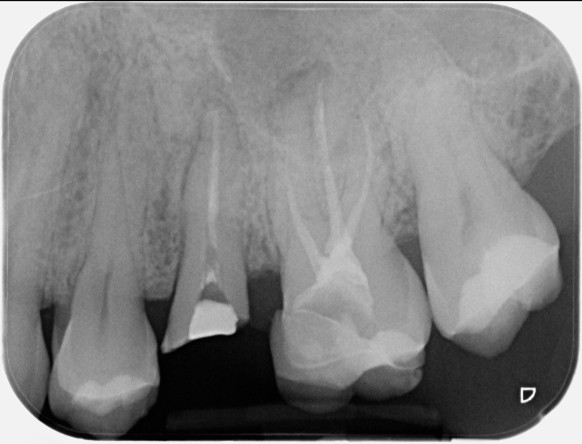

Multi-disciplinary: root canal treatment, molar apicectomy and bone regeneration

Pre-operative X-ray

Post-operative X-ray